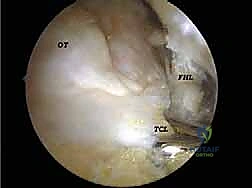

* تحرير وتنظيف وتر (FHL): إذا كان الوتر ملتهباً ومحاصراً، يتم قطع سقف النفق الليفي لتحريره، وإزالة الأنسجة الملتهبة (Tenosynovectomy) لضمان انزلاقه بحرية.

* إزالة الأجسام الحرة والنتوءات العظمية: يتم التقاط الشظايا العظمية أو الغضروفية وإخراجها، واستخدام أدوات دقيقة (Burr) لتنعيم النتوءات العظمية التي تسبب الاحتكاك.

الخطوة 3: الاستكشاف البانورامي (Diagnostic Arthroscopy)

يتم إدخال كاميرا المنظار عالية الدقة (4K) عبر أحد المداخل، بينما تُستخدم الأدوات الجراحية الدقيقة في المدخل الآخر. تتيح الكاميرا للدكتور هطيف رؤية الهياكل الداخلية مكبرة عشرات المرات على شاشة عملاقة، مما يسمح بتقييم دقيق للمفاصل، الأوتار، والأربطة.

* استئصال العظم الزائد (Os Trigonum Excision): يتم فصل العظم الزائد بحذر عن الأنسجة المحيطة واستخراجه بالكامل، مما يزيل سبب الانحشار والألم فوراً.